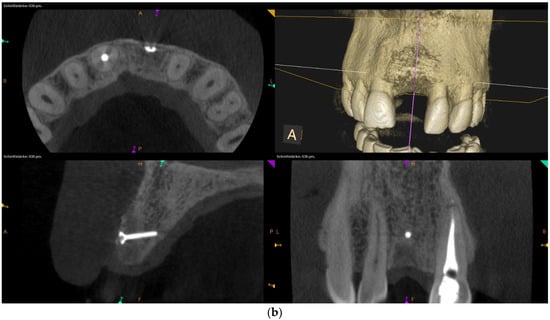

Over-contouring was defined as an over-augmentation of the alveolar process beyond the extent of the adjacent bone level (Figure 1). The reason for over-augmenting the alveolar process is often an anticipated shrinkage of the bone substitution material during the healing phase. Two patients were selected as examples to illustrate the term “over-contouring”. Patient 1 showed a Class III defect in the maxilla, and the alveolar ridge augmentation performed for correction was over-contoured (Figure 2). Patient 2 also showed a Class III defect in the maxilla, but the alveolar ridge augmentation performed for correction remained at the level of the surrounding bone (Figure 3).

Figure 2.

Clinical example of over-contouring. (a) Class III defect with pronounced vestibular deficit and minor vertical deficit. (b) Post-OP: Attachment of a cortico-cancellous allogeneic bone block. Vestibular over-contouring with the cortical plate and vertical over-contouring of the block can be seen. The block protrudes over the limbus alveolaris, i.e., over the bone border of the adjacent teeth. (c) After 5 months: the over-contoured portion of the cortical portion of the block was not resorbed, but part of the cancellous portion of the block was palatally resorbed away. (d) The over-contoured block penetrates the mucosa. The cortical portion is revealed.